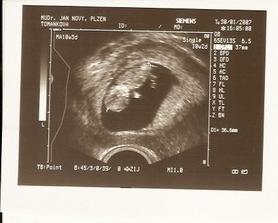

SRPŇÁTKA 2007 - fotky UTZ

album věnované mimískům, které se narodí v srpnu 2007 a jejich maminkám ze "Společného termínu SRPEN"